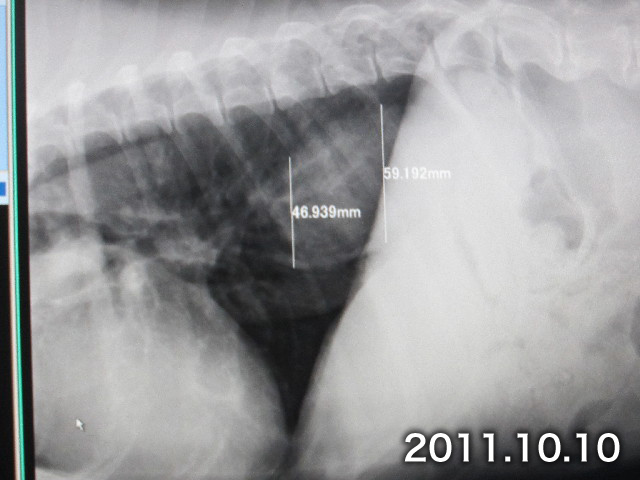

●レントゲンでQちゃん(食道の腫瘍)の大きさも調べてみました。

5月3日と比べて食道側が1.767ミリ。胃の側が0.761ミリ大きくなっていましたが、『ほとんど大きくなっていない』です!(^^)!

【10月10日(今日)】

今回は同じ背骨の場所で比較しているので大きさの変動がわかりやすいです。